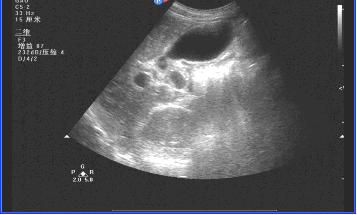

在超声图像上,慢性肝炎在不同程度的时期有不同程度的表现。

三、慢性肝炎肝硬化时的超声影像:

肝缩小,被膜不光滑,肝回声结节样增粗,门静脉扩张,腹水。